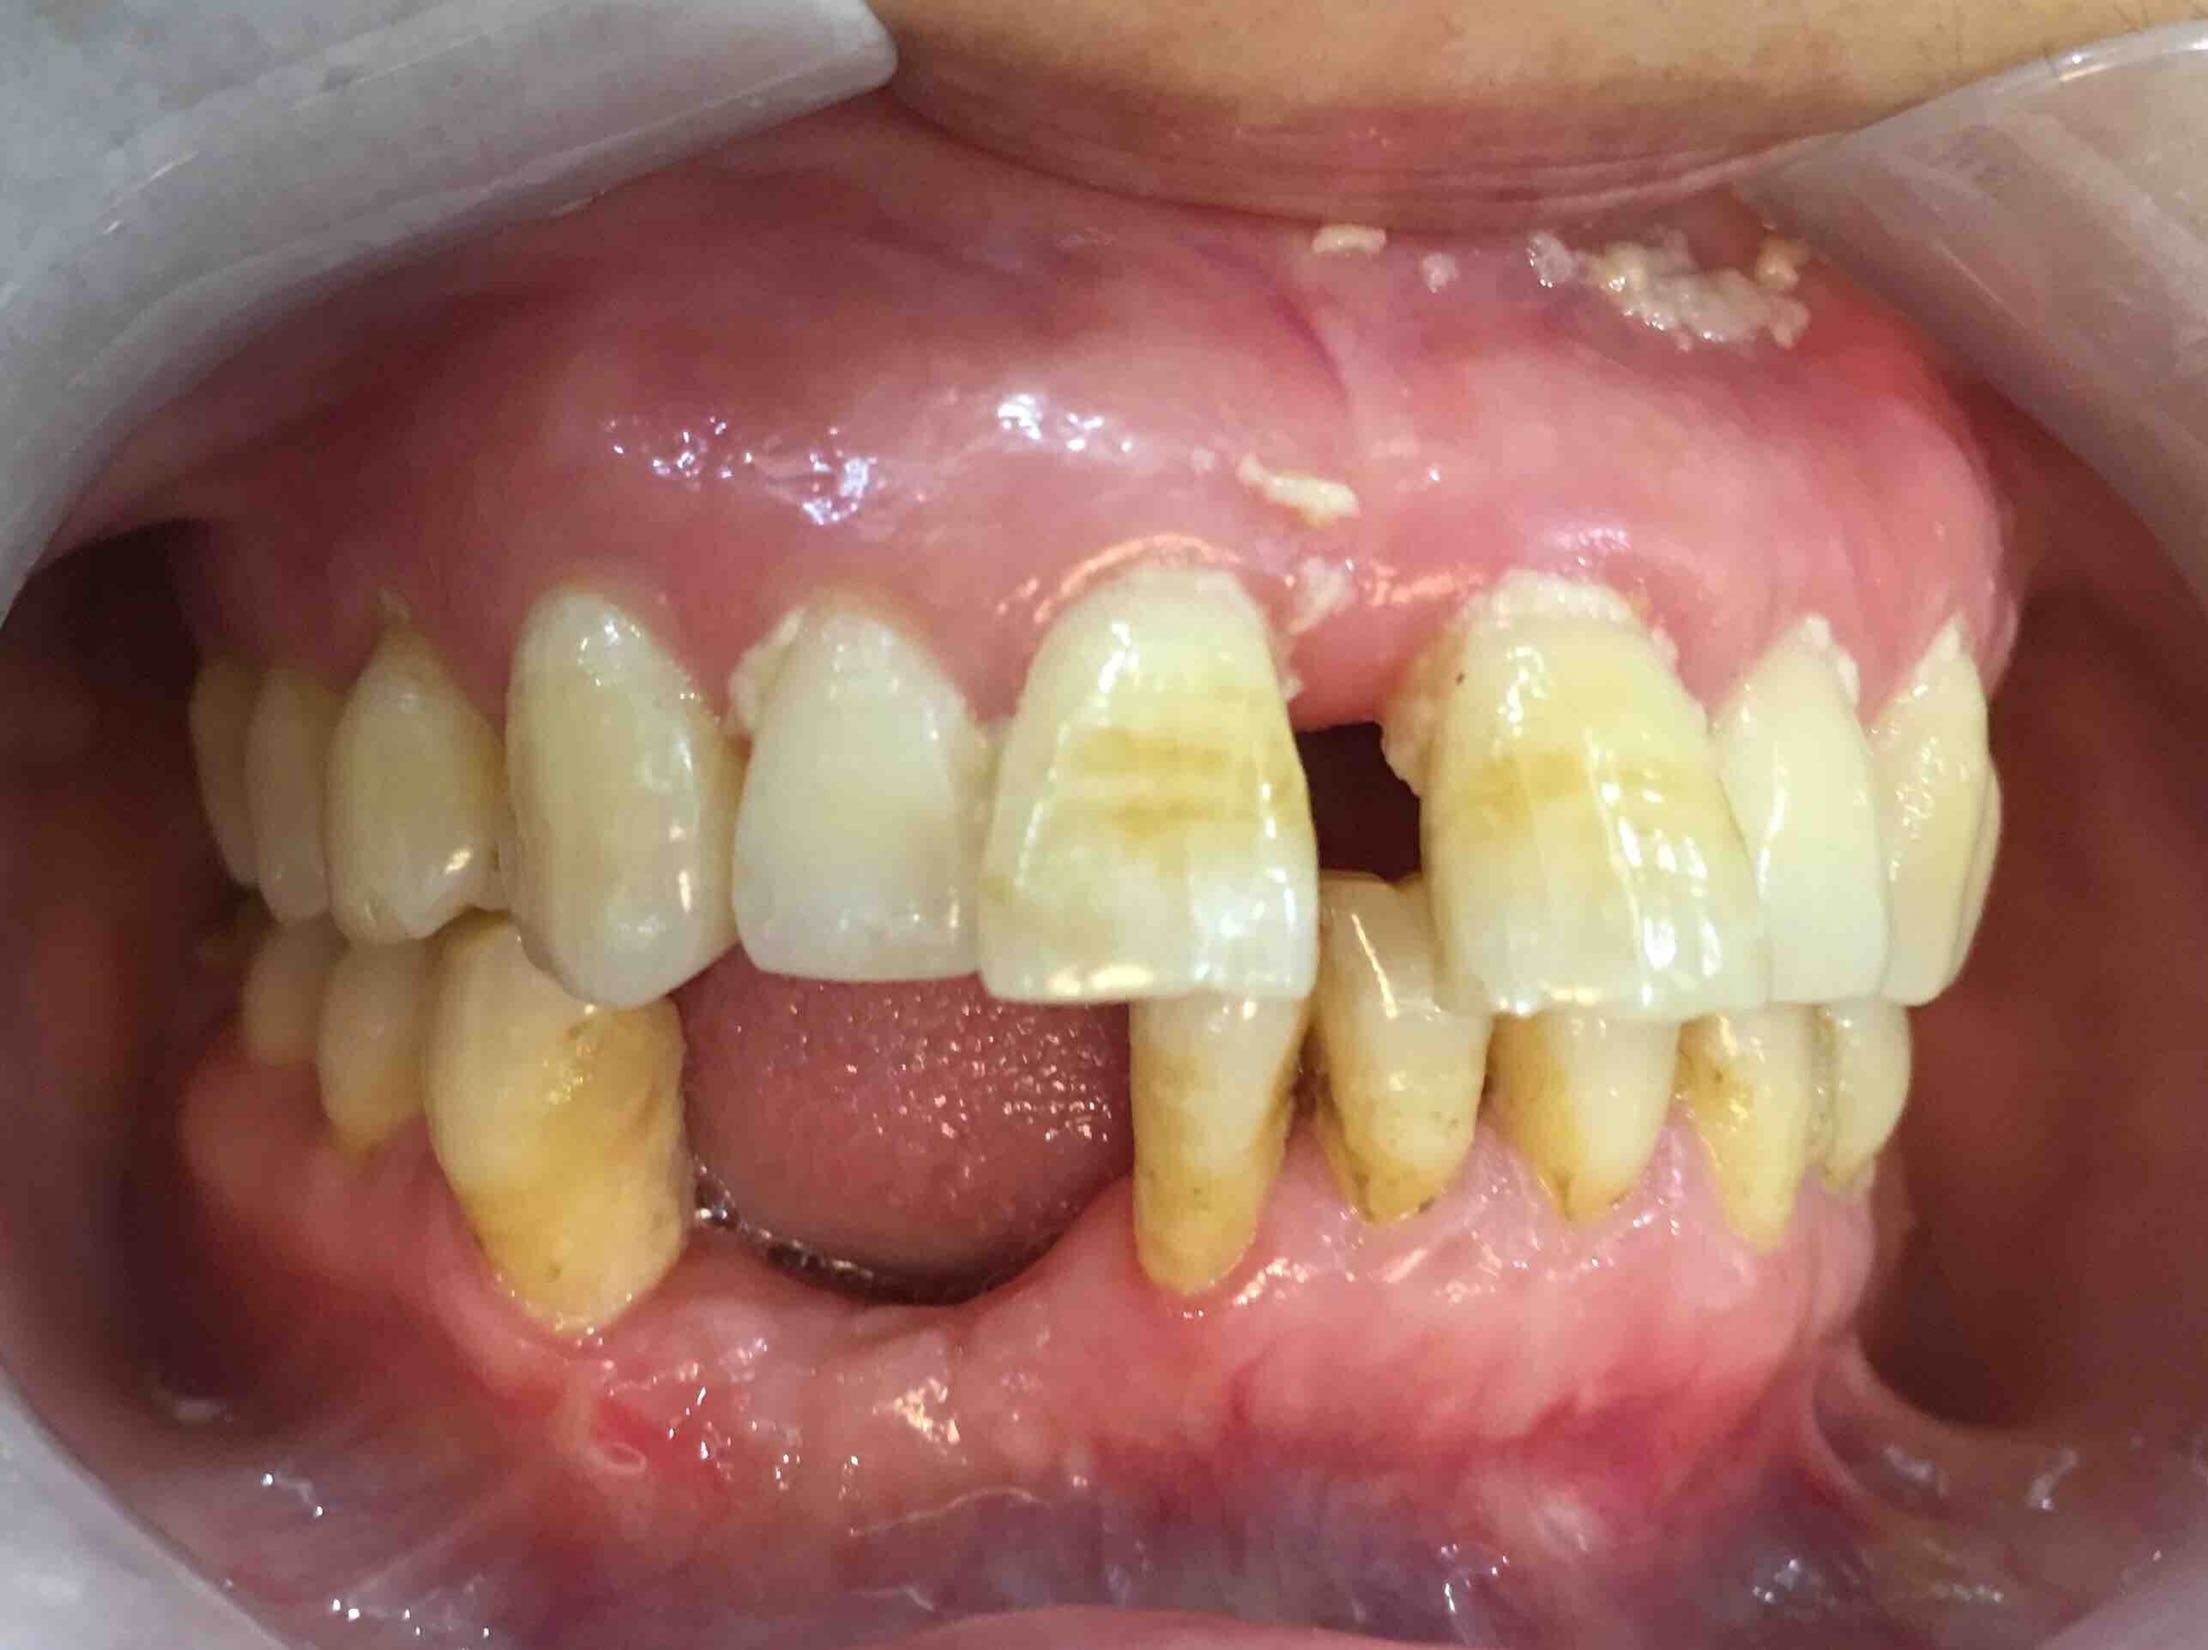

三个月后,牙龈成型前,口内照,未完待续……